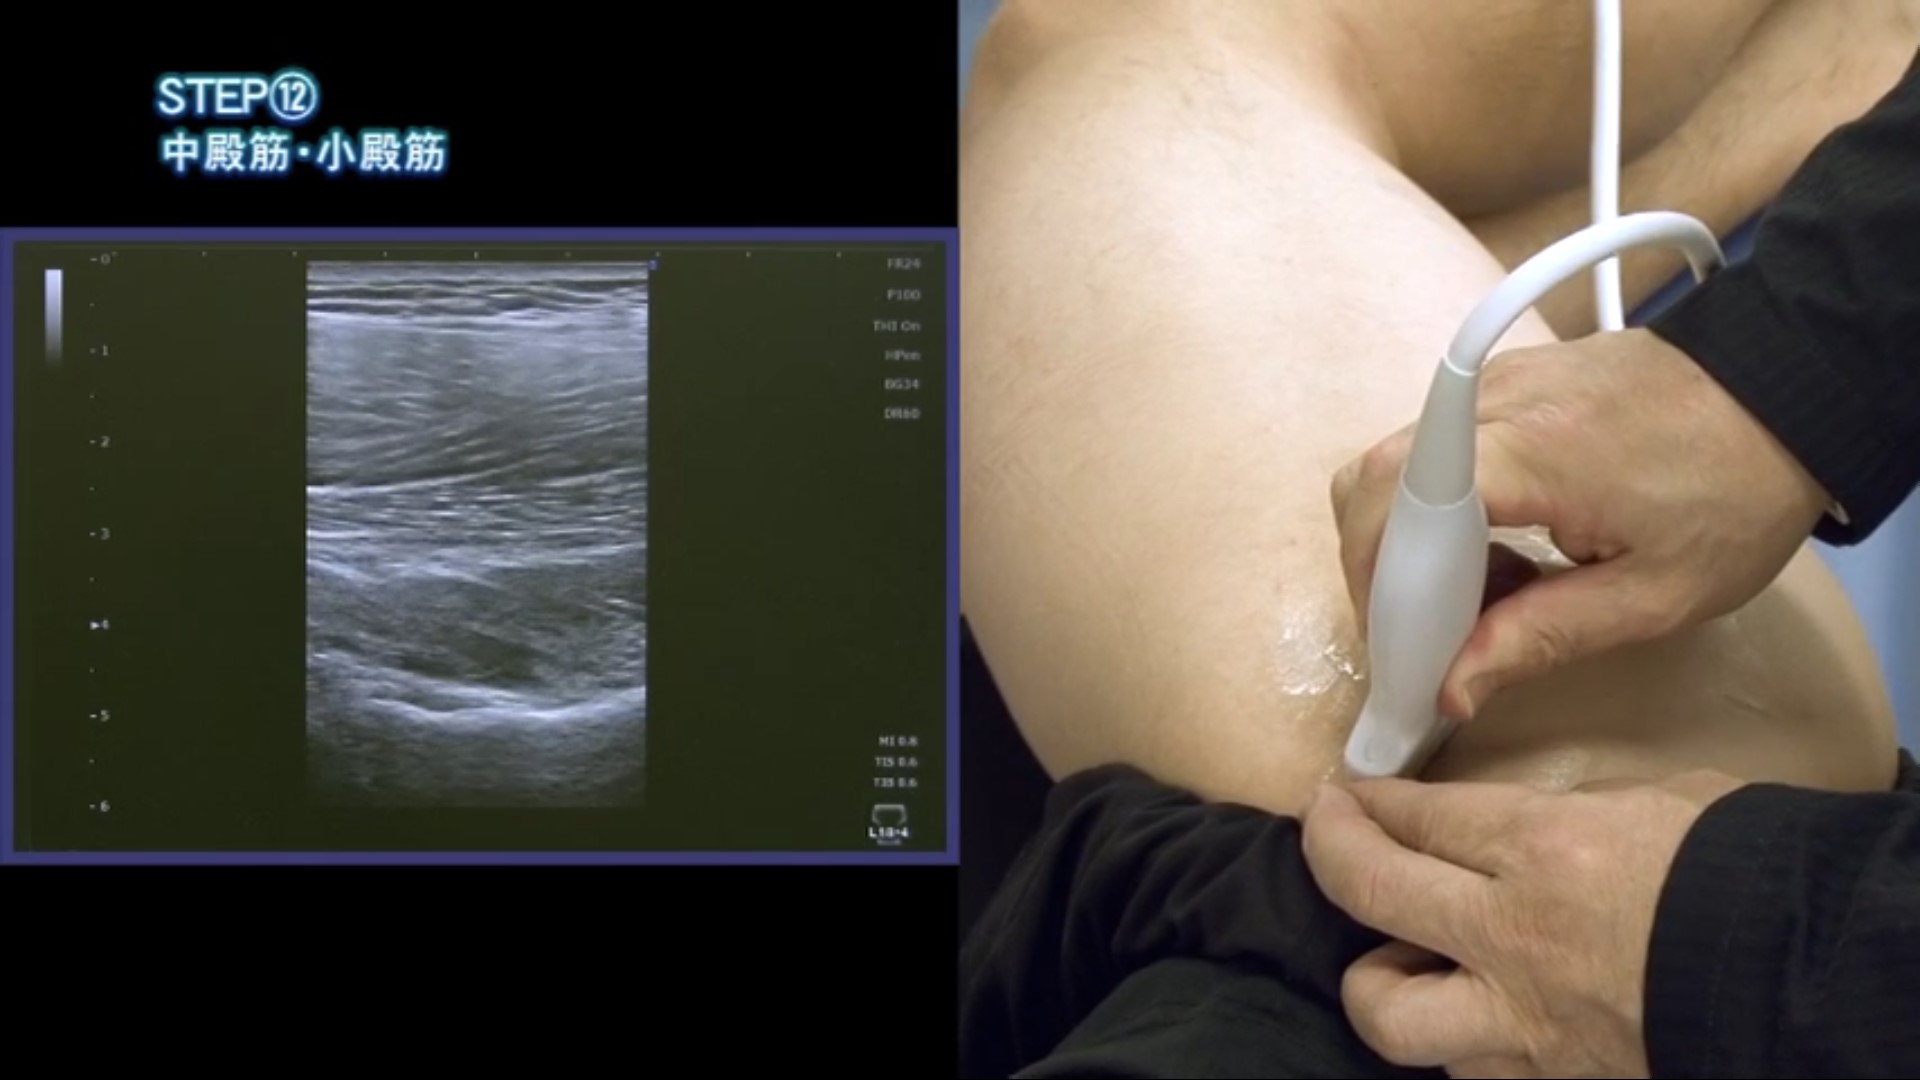

STEP(11) 大腿骨頭前方組織/STEP(12) 中殿筋・小殿筋

07分25秒